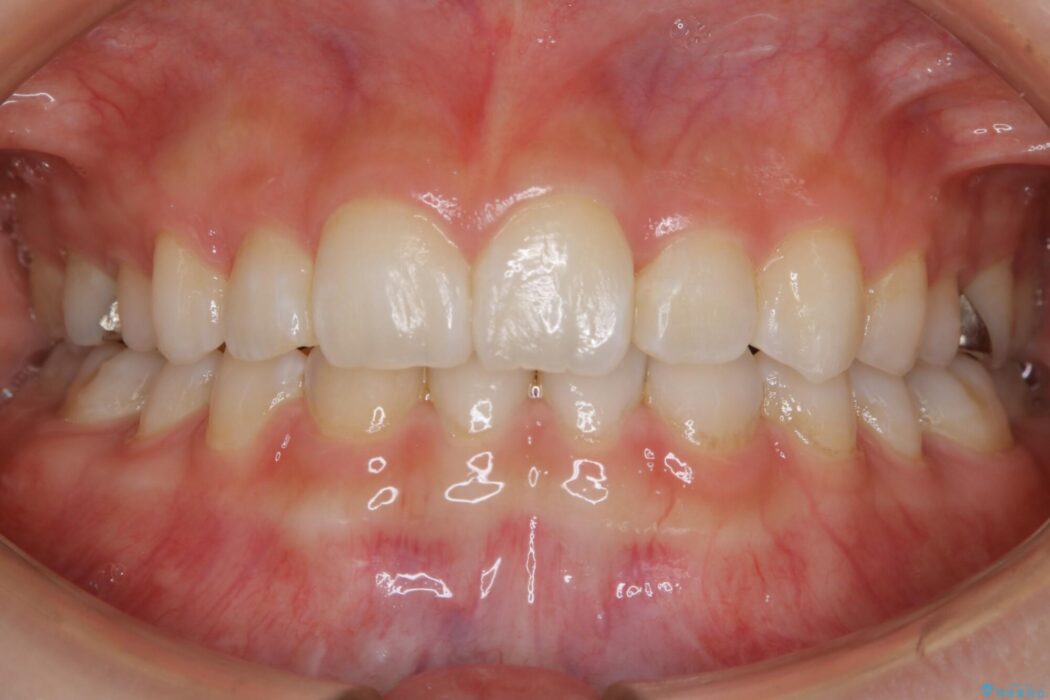

飛び出た八重歯による歯列のガタガタを主訴に来院されました。

笑った時の歯の見た目がきれいになりとても喜んでいただけました。